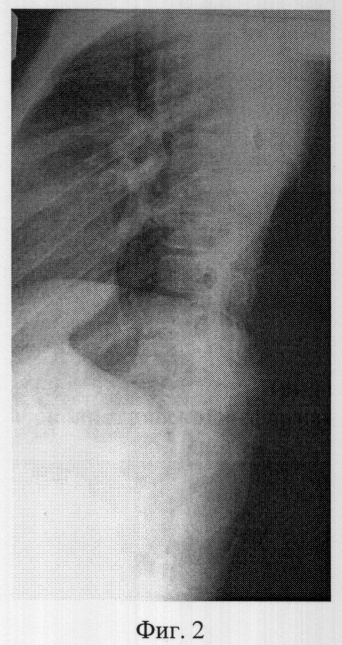

Фиг.2 – рентгенограмма в боковой проекции сколиотически измененного позвоночника больной К. до операции (грудопоясничная локализация);

Пример 1. Больная К., 14 лет, 15.10.05 поступил в клинику детской ортопедии СарНИИТО по поводу диспластического прогрессирующего нестабильного правостороннего грудопоясничного компенсированного сколиоза IV степени.

В СарНИИТО ей были выполнена рентгенография в стандартных проекциях: фасная (фиг.1) и боковая (фиг.2) рентгенограммы.

По фасной рентгенограмме определены показатели позвоночника:

– угол сколиотической деформации по Кобб: стоя – 73°, лежа – 64°;

– индекс стабильности по Казьмину – 0.86;

– определена протяженность дуги в 13 позвонков (от Th5 до L5),

– вершина деформации Тh12.

По рентгенограммам проведена оценка зрелости костной ткани позвоночника: тест Риссера составил R-4, кольцевые апофизы тел позвонков по дуге искривления определяются лишь у позвонка Th5, что свидетельствует завершенности роста у больной.